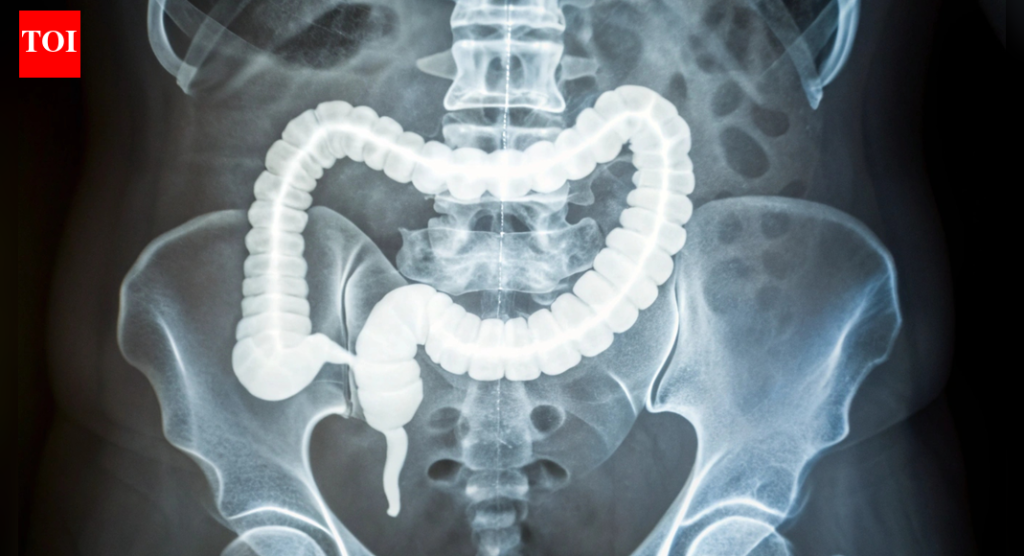

कोलोरेक्टल कॅन्सर आधी दिसल्यामुळे एक कडक कोलन अलार्म का वाढवत आहे: ते कसे ओळखावे

कोलोरेक्टल कॅन्सर हा वृद्धापकाळाचा आजार मानला जात असे, जो बहुतेक 50 नंतर आढळतो, परंतु गेल्या काही दशकांमध्ये, कोलोनोस्कोपीसारख्या व्यापक तपासणीमुळे त्या गटातील प्रकरणे-आणि मृत्यू कमी झाले आहेत. पण आता – 50 वर्षाच्या आधी होणारा कोलोरेक्टल कॅन्सर, जो 2020 पासून यूएस मधील सर्व निदानांपैकी 12% आहे. दर झपाट्याने वाढले आहेत, अद्याप एकही दोषी पूर्णपणे स्पष्ट केलेला नाही.बरेच लोक आधुनिक जीवनशैलीकडे निर्देश करतात: प्रक्रिया केलेले अन्न जड आहार, मध्यभागी अतिरिक्त पाउंड आणि पर्यावरणीय घटक जे कालांतराने आतडे चिडवतात. ही जुनाट सूज तात्काळ वेदना देत नाही परंतु शांतपणे तयार होते – संकटाचा टप्पा निश्चित करते. अंदाजानुसार 2030 पर्यंत ही संख्या दुप्पट होऊ शकते, विशेषत: त्यांच्या 20 ते 40 च्या दशकातील लोकांमध्ये, डॉक्टरांना तपासणी कधी सुरू करायची यावर पुनर्विचार करण्यास प्रवृत्त करते.

अलीकडील अभ्यासात कोलोरेक्टल कॅन्सर तरुण प्रौढांमध्ये का अधिक वेळा दिसून येत आहे यावर प्रकाश टाकला आहे, संभाव्य लवकर चेतावणी चिन्ह म्हणून कडक कोलनकडे निर्देश करते. अनेक वर्षांच्या निम्न-दर्जाच्या जळजळांमुळे चाललेले- हे ऊतक कडक होणे ट्यूमर पकडण्यासाठी आणि जलद वाढण्यासाठी योग्य वादळ निर्माण करते असे दिसते. संशोधनामागील तज्ञांना आशा आहे की हे निष्कर्ष 50 वर्षांखालील लोकांसाठी तयार केलेल्या चांगल्या तपासणी आणि उपचारांसाठी दरवाजे उघडतील.सुरुवातीचे नमुने वेगळे होते: एकूणच अधिक कठोर. सखोल खोदल्यावर, टीमला कोलेजनचे जाड, लांब पट्टे आढळले, प्रथिने जे डाग पडताना तयार होतात. हे कोलेजन अधिक परिपक्व आणि सुबकपणे संरेखित होते, वारंवार जळजळ होण्याची चिन्हे त्याची छाप सोडतात. जीन चाचण्यांनी याची पुष्टी केली, कोलेजन प्रक्रियेसाठी वाढलेली क्रिया, नवीन रक्तवाहिन्यांची वाढ-आणि तरुण रुग्णांच्या ऊतींमध्ये चालू असलेली रोगप्रतिकारक प्रतिक्रिया दर्शविते.

येथे ते आकर्षक होते. आतड्यात तीव्र चिडचिड झाल्यामुळे स्तनाच्या किंवा स्वादुपिंडाच्या कर्करोगाप्रमाणेच कोलनच्या भिंती घट्ट होतात. पेशी याकडे दुर्लक्ष करत नाहीत; त्यांना मेकॅनोट्रांसडक्शन नावाच्या प्रक्रियेद्वारे पिळणे जाणवते. मेकॅनिकल स्ट्रेस फ्लिप पेशींच्या आत स्विच करतात, जैवरासायनिक सिग्नल स्पार्क करतात जे त्यांना विभाजित आणि पसरण्यास सांगतात.मुद्दा सिद्ध करण्यासाठी, शास्त्रज्ञांनी पृष्ठभागावर कोलोरेक्टल कर्करोगाच्या पेशी वाढवल्या आणि वेगवेगळ्या कडकपणाच्या पातळीची नक्कल केली. कडक असलेल्यांवर, पेशी जलद गुणाकार करतात. त्यांनी अगदी रूग्णांच्या पेशींमधून 3D ऑर्गनॉइड्स—मिनी ट्यूमर मॉडेल्स—बनवले, आणि जे कडक पायावर आहेत ते अधिक मोठे आणि जलद झाले. हे सूचित करते की कठोर वातावरण केवळ कर्करोग वाढू देत नाही; हे सामान्य पेशींना प्रथमतः घातकतेकडे ढकलू शकते.

एमिना हुआंग, येथे शस्त्रक्रिया प्राध्यापक UT नैऋत्य आणि अभ्यासाचे नेते, याला गेम चेंजर म्हणतात. कोलन आणि गुदाशय शस्त्रक्रियेतील तिच्या पार्श्वभूमीसह, ती लक्षात घेते की ट्यूमरच्या आधी जडपणा कसा येऊ शकतो, एक नवीन जोखीम मार्कर देते. तिचे सहकारी जॅकोपो फेरुझी, एक बायोइंजिनियरिंग तज्ञ, हायलाइट करतात की हे नमुने टिश्यू स्केलवर खरे आहेत, डाग टिश्यूला वोन्की सेल सिग्नलशी जोडतात.हे काम प्रगत विज्ञान मध्ये दिसून आले, ज्यामध्ये बायोमेकॅनिकल बदलांच्या संपूर्ण तपशीलांसह सुरुवातीच्या-सुरुवातीच्या प्रकरणांसाठी अद्वितीय आहे. मेमोग्राम स्तनाची घनता मोजतात त्याप्रमाणे कडकपणा चाचण्या नियमित होत असल्याची कल्पना हुआंगने केली आहे. इतर कॅन्सरच्या चाचण्यांमध्ये असलेल्या शक्ती-संवेदनशील मार्गांना अवरोधित केल्याने येथे देखील वाढ थांबू शकते.